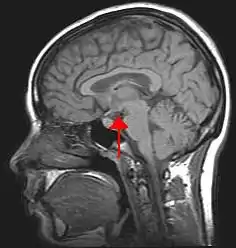

![]() Location of the human hypothalamus | |

![]() Location of the hypothalamus (cyan) in relation to the pituitary and to the rest of the brain | |

The hypothalamus (pl.: hypothalami; from Ancient Greek ὑπό (hupó) 'under', and θάλαμος (thálamos) 'chamber') is a small part of the brain that contains a number of nuclei with a variety of functions. One of the most important functions is to link the nervous system to the endocrine system via the pituitary gland. The hypothalamus is located below the thalamus and is part of the limbic system.[1] It forms the ventral part of the diencephalon. All vertebrate brains contain a hypothalamus.[2] In humans, it is the size of an almond.